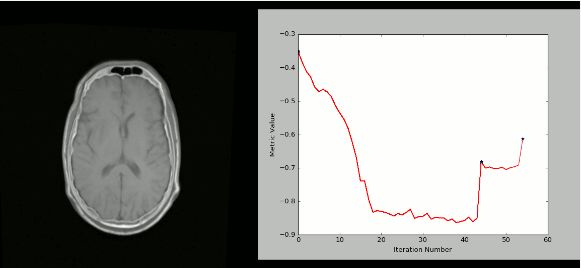

SimpleITK是一个基于ITK构建的简化层,旨在促进其在快速原型设计,交易以及解释语言方面的应用。”它也是一个图像分析工具包,具有大量组件,支持一般过滤操作,图像分割和配准。SimpleITK是用C ++编写的,但它可用包括Python在内的大量编程语言进行操作。

使用SimpleITK和Python创建可视化的严格CT / MR配准过程: